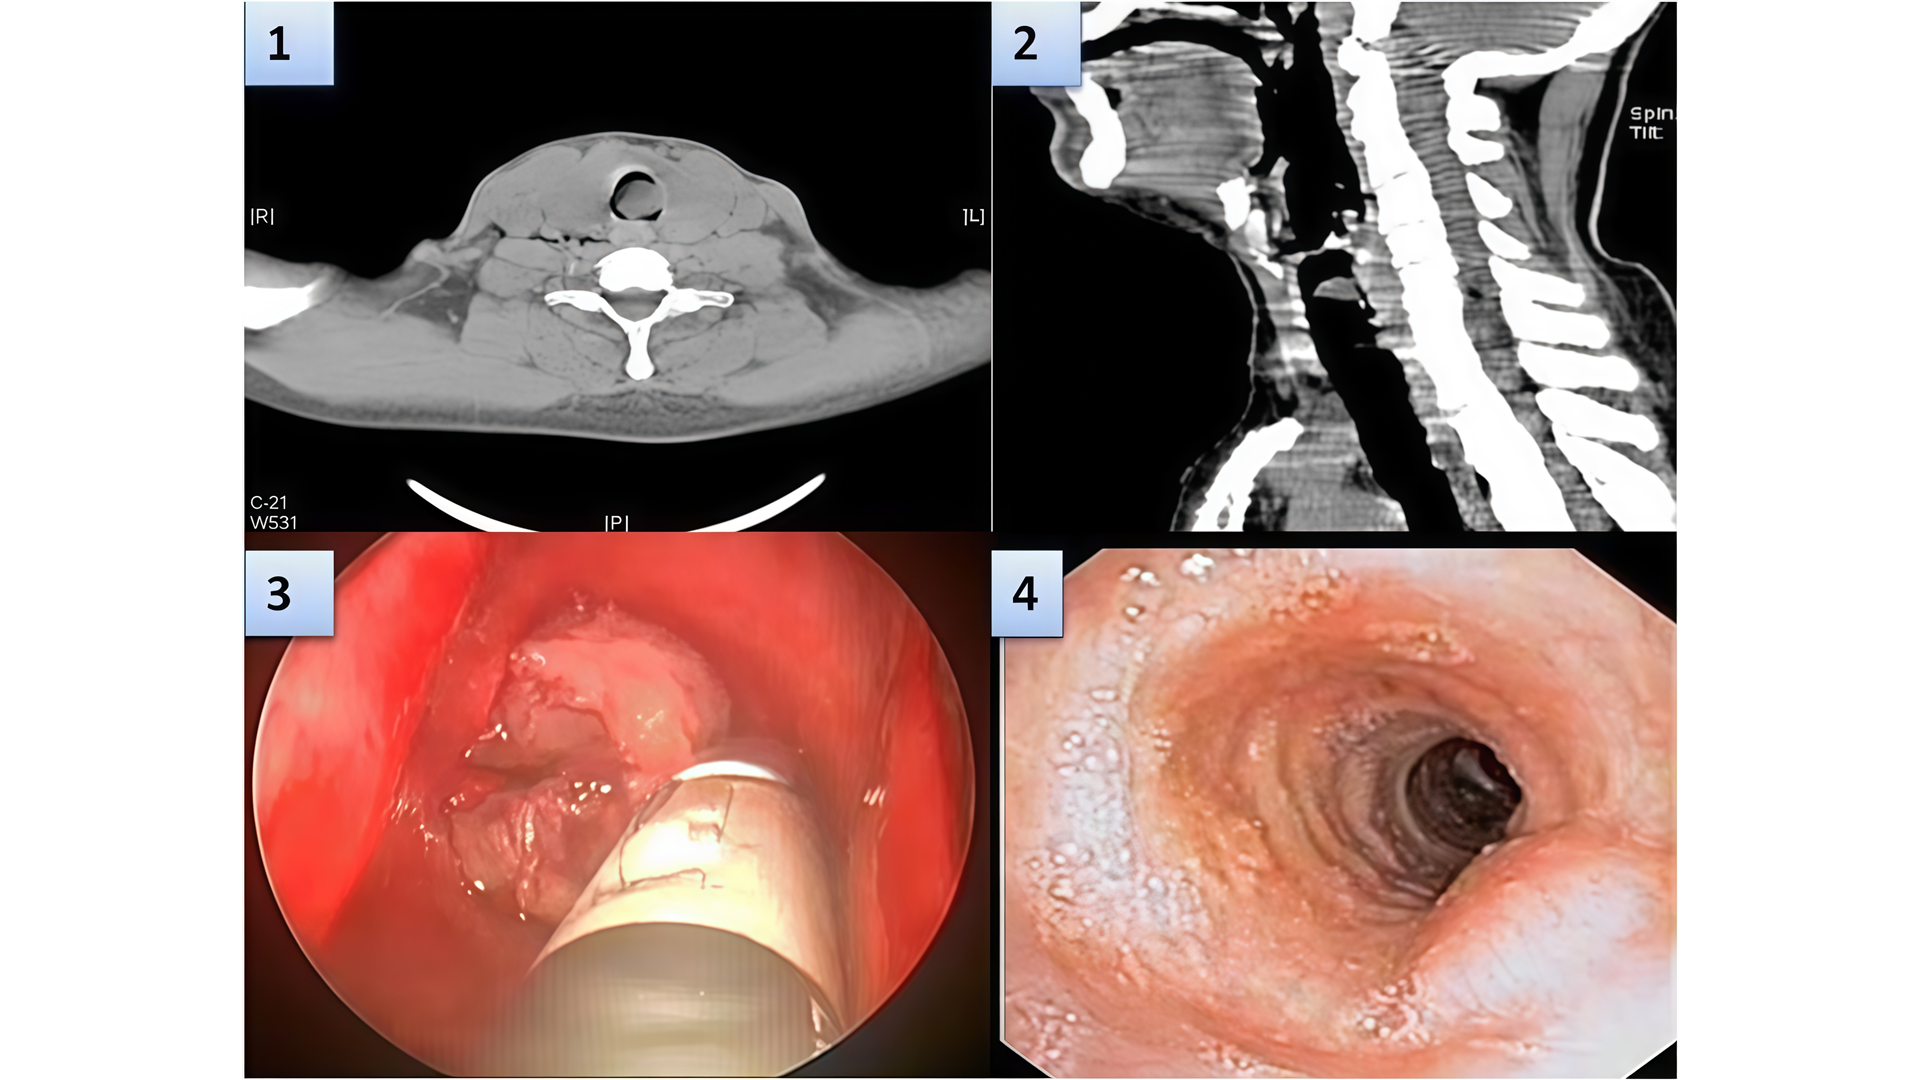

Первичный рак трахеи: редкая, но важная патология в дифференциальной диагностике обструктивных заболеваний дыхательных путей

- Чрезвычайная редкость: Первичные злокачественные опухоли трахеи составляют лишь около 0,2% от всех онкологических заболеваний. Заболеваемость оценивается примерно в 0,1 случая на 100 000 человек в год.

- Основные гистологические типы у взрослых:

✔ Плоскоклеточный рак (45% случаев, наиболее частая форма).

✔ Аденокистозная карцинома (цилиндрома).

✔ Реже встречаются: мелкоклеточный рак, аденокарцинома, саркома.

✔ Важно: У взрослых до 90% первичных опухолей трахеи являются злокачественными. - Диагностическая ловушка: Клиническая картина часто неспецифична и маскируется под доброкачественные заболевания:

✔ Для верификации диагноза обязательны гистологическое исследование и тщательное лучевое обследование (КТ, МРТ, ПЭТ/КТ) для поиска возможного первичного очага в других органах.